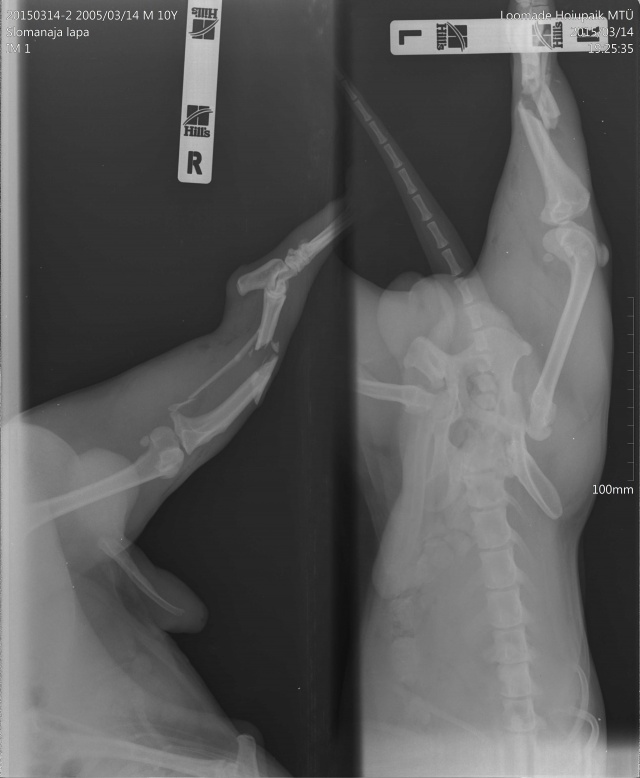

Koer on opereeritud.

Tagumise käpa luumurd.

Koerake sattus varjupaika vigastatud käpaga. Ülevaatusel selgus, et koera käpal on mitmekordne luumurd. Pidime paigaldama ka kateetri, kuna ta ei saanud pissida (ilmselt autolöögist põhjustatud kusepõie atoonia).

Homme opereerime. Palun aidake! Tema ravi ning rehabiliteerimine saab olema pikk ja raske.

Собака поступила в приют с множественным переломом ноги. Не могла пописать (видимо был удар машины и, как результат, атония мочевого пузыря). Нога в очень тяжёлом состоянии, и завтра мы кладём собаку на операционный стол.

Просим вашей помощи, потому что операция и последующая реабилитация будут довольно сложными и долгими!